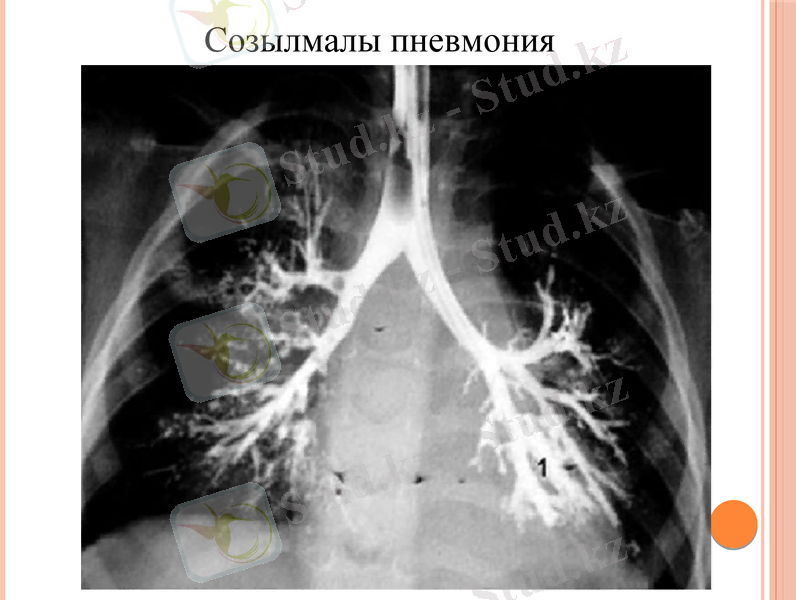

Міндетті растайтын диагностикалық әдістер радиографиялық тексеруден

тұрады (өкпенің радиографиясы, бронхография), эндоскопиялық

(бронхоскопия), функционалды (спирометрия), зертханалық тексеру

(Емен, қан биохимиясы, қақырықты микроскопиялық және

бактериологиялық талдау) .

Созылмалы пневмонияны тексеру кезінде 2 проекциядағы өкпе

рентгенографиясы өте маңызды. Радиографияларда келесі белгілер

анықталуы мүмкін: өкпе лобының көлемінің төмендеуі, деформация және

өкпелік құрылымның қаттылығы, фокус көлеңкелері (карнизиямен),

перибрончальді инфильтрация, плевральді өзгерістер және т. б.

Жедел фазада пневмосклероздың фонында жаңа инфильтративтік

көлеңкелер табылған. Бронхографиялық мәліметтер бронхит бронхитін

көрсетеді (контурлардың дұрыс емес болуы және контрастты біркелкі

таратуы анықталған) .